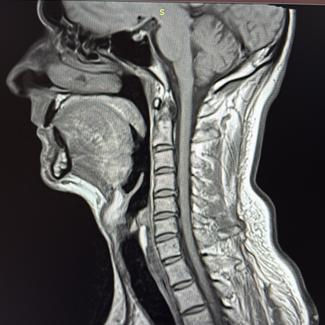

Dr Marc Bony

Quiropráctico

El Dr. Marc Bony cuenta con más de 20 años de experiencia y ha ayudado muchos pacientes a vivir sin dolores y un bienestar de salud.